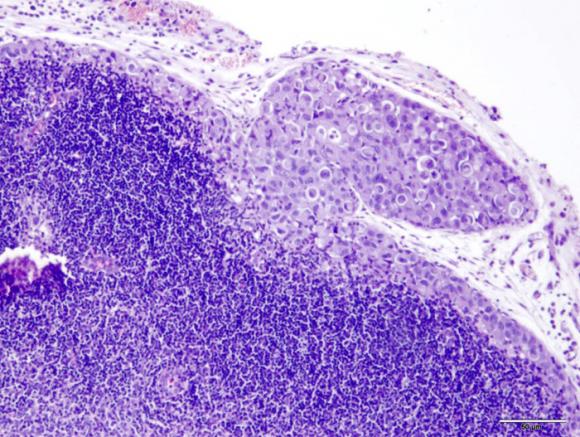

Lo que hicieron Paula Roberti, Marcela Barrio, Mordoh y otros colegas fue cultivar células provenientes de un cáncer de mama humano “triple negativo”, las cuales fueron luego inoculadas en ratones de experimentación que permiten el crecimiento de células humanas sin rechazarlas. “Las células resultaron ser metastásicas en el ratón, pudiendo invadir los ganglios: un proceso semejante al que ocurre en la enfermedad humana”, precisó Mordoh. Tras varios ciclos de crecimiento de las células metastásicas, los científicos lograron obtener células significativamente más agresivas.

Para profundizar en los mecanismos moleculares que subyacen al proceso, los científicos realizaron una comparación entre las células originarias y las metastásicas mediante una tecnología que permite evaluar los cambios de ciertas proteínas celulares.

El doctor José Mordoh, Jefe del Laboratorio de Cancerología del Instituto Leloir y Director del Centro de Investigaciones Oncológicas de la Fundación Cáncer, y sus colegas crearon un modelo que permite estudiar el cáncer de mama más agresivo.